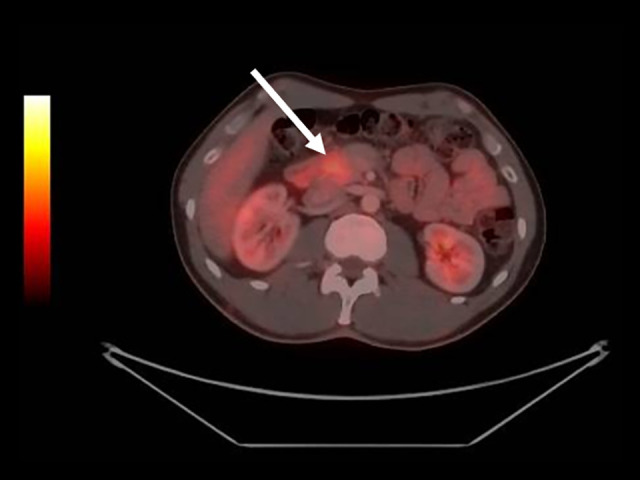

免疫疗法近年来呈指数增长,其相关副作用的研究也呈指数增长。尽管对免疫治疗的广泛反应已被描述,但免疫介导的局灶性胰腺炎的报道仍然很少。与免疫检查点抑制剂相关的自身免疫性胰腺炎发生的原因是T淋巴细胞的过度活化,T淋巴细胞对胰腺细胞起作用,引起炎症。病例报告:本病例报告描述了一位先前健康的41岁男性,诊断为转移性黑色素瘤伴腹股沟淋巴结转移。患者接受了1年的纳武单抗辅助治疗,并具有良好的耐受性。该治疗暂停1年后,淋巴结和腹膜复发发生,导致开始伊匹单抗和纳武单抗联合治疗,随后维持纳武单抗,导致完全缓解。经过10个疗程的纳武单抗治疗后,PET-CT和MRI发现胰腺头部病变,怀疑为原发性肿瘤。患者无症状,肿瘤标志物正常,淀粉酶和脂肪酶水平升高。内镜下超声引导活检排除原发性胰腺癌,发现与免疫治疗相关的中度活动性慢性炎症。尼武单抗治疗中断2周,期间胰酶水平改善。此后恢复治疗。患者继续每月应用纳武单抗,保持完全缓解。成像或实验室检查结果无变化。结论:由于缺乏皮质类固醇干预,炎症的自限性,尽管继续使用免疫治疗,但缺乏炎症复发,该病例是非典型的自身免疫性胰腺炎。

BACKGROUND Immunotherapy has seen an exponential increase recently, as has the study of its associated adverse effects. Although a wide range of reactions to immunotherapy has been described, reports of immune-mediated focal pancreatitis remain rare. Autoimmune pancreatitis related to immune checkpoint inhibitors occurs because of the hyperactivation of T lymphocytes, which act against pancreatic cells, causing inflammation. CASE REPORT This case report describes a previously healthy 41-year-old man with a diagnosis of metastatic melanoma with inguinal lymph node metastasis. The patient underwent 1 year of adjuvant treatment with nivolumab and had excellent tolerance. After a 1-year suspension of this treatment, nodal and peritoneal recurrence occurred, leading to the initiation of combined therapy with ipilimumab and nivolumab, followed by maintenance nivolumab, resulting in a complete response. After 10 cycles of nivolumab, PET-CT and MRI identified a lesion in the head of the pancreas, which was suspected to be a primary neoplasm. The patient was asymptomatic, with normal tumor markers and elevated amylase and lipase levels. An endoscopic ultrasound-guided biopsy was performed to rule out primary pancreatic cancer, revealing moderately active chronic inflammation associated with immunotherapy. Nivolumab treatment was interrupted for 2 weeks, during which pancreatic enzyme levels improved. Treatment was resumed thereafter. The patient continued with monthly nivolumab applications, maintaining a complete response. without changes in imaging or laboratory test results. CONCLUSIONS This case is atypical for autoimmune pancreatitis owing to the absence of corticosteroid intervention, self-limiting nature of inflammation, and lack of inflammatory recurrence despite the continued use of immunotherapy.